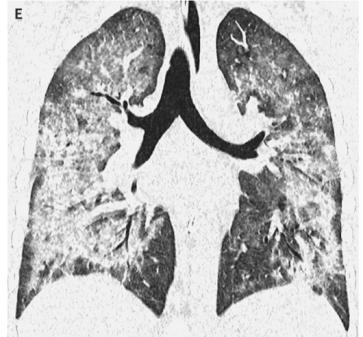

- 98%的患者出现呼吸道症状,81%出现胃肠道症状,100%出现全身症状。所有患者均有胸部成像双侧浸润;

图1. 双肺浸润

- 患者的肺损伤可能表现为多种形式,比如急性嗜酸性粒细胞性肺炎、组织性肺炎、脂质性肺炎、急性呼吸窘迫综合征、弥漫性肺泡出血、过敏性肺炎以及罕见的巨细胞间质性肺炎等;